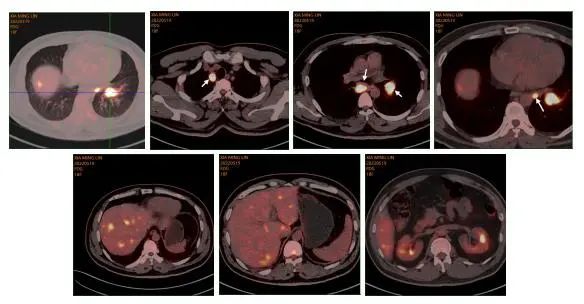

PET-CT(2022.5.19):左下肺背段近肺门分叶状结节,约3.0×2.3cm,放射性摄取异常增高,SUVmax=11.4;右上气管旁、隆突下、后纵隔降主动脉左前及左侧肺门肿大淋巴结,大者2.4*1.9cm,放射性浓聚,SUVmax=11.5。肝内散在多发略低密度影,边界不清,放射性摄取增高,SUVmax=7.0。

图1.PET-CT图像